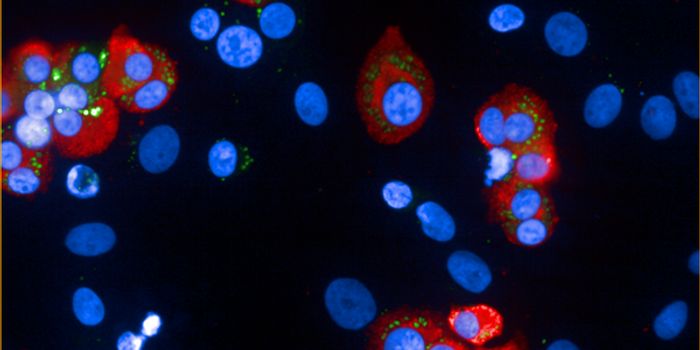

MAY 22, 2017ImmunologyThree new approaches to anticancer drug therapy were combined in a recent study to simultaneously maximize destruction o ...